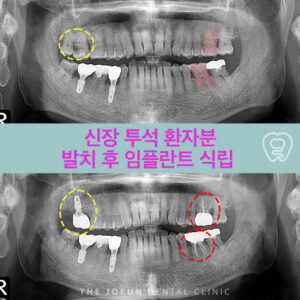

달서구임플란트잘하는곳 치조정 접근법을 통한 상악동 뼈이식술 임플란트는 치아가 빠진 부위에 티타늄으로 만들어진 인공치근을 치조골에 식립하여 상부에는 크라운을 제적하여 연결하는 보철치료르 말합니다. 치아의 뿌리부터 머리까지 자연치와 비슷한 모양으로 심미성이 뛰어나고, 자연치와 유사한 기능을 보이는데요. 이는 잇몸뼈에 식립체를 직접 식립하게 되는데 진행을 위해서는 치조골의 양과 상태가 충분해야 합니다. 치아를 상실했어도 치조골 상태가 더보기…